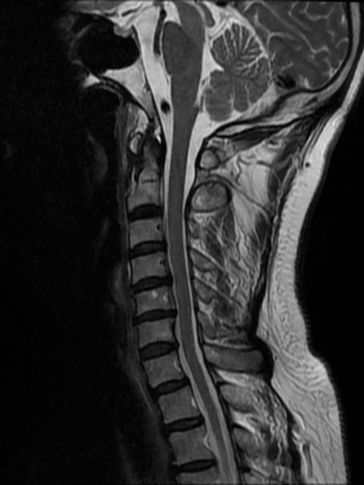

MRI Cervical Spine

Upper limb numbness, weakness, cervical spondylosis, etc.